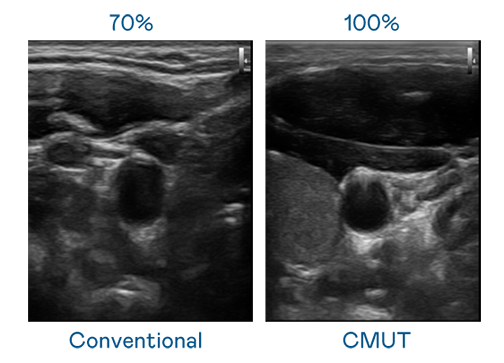

CMUT 技术是一种用电容式微机电元件来产生超音波讯号的技术。与传统 PZT 压电式技术相比,CMUT 频宽增加 30%,更宽频的超音波讯号让影像解析度大幅提升,是实现高影像品质医疗超音波扫描、促进精准医疗发展的关键技术。

大频宽带来超清晰影像

超音波影像的解析度高低,首先取决于探头能发出的讯号频宽。PG国际 CMUT 可提供高清晰的超音波讯号,提供高频宽、高灵敏度、影像纹理细节更高的超音波影像,协助医护人员缩短影像判读时间及利用精准的医疗影像进行诊断。